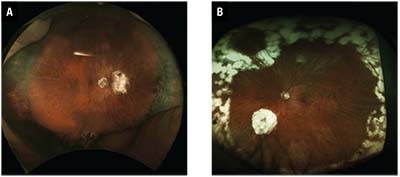

| Figure 1. A typical case that would be included in the CPT code 67108 series, retinal detachment (RD) repair with vitrectomy (A). Postoperative photography (B) shows outcome of macula-off RD, resulting in complete Recovery of central vision and subjectively better vision post-RD repair because of vitrectomy and floater removal. |